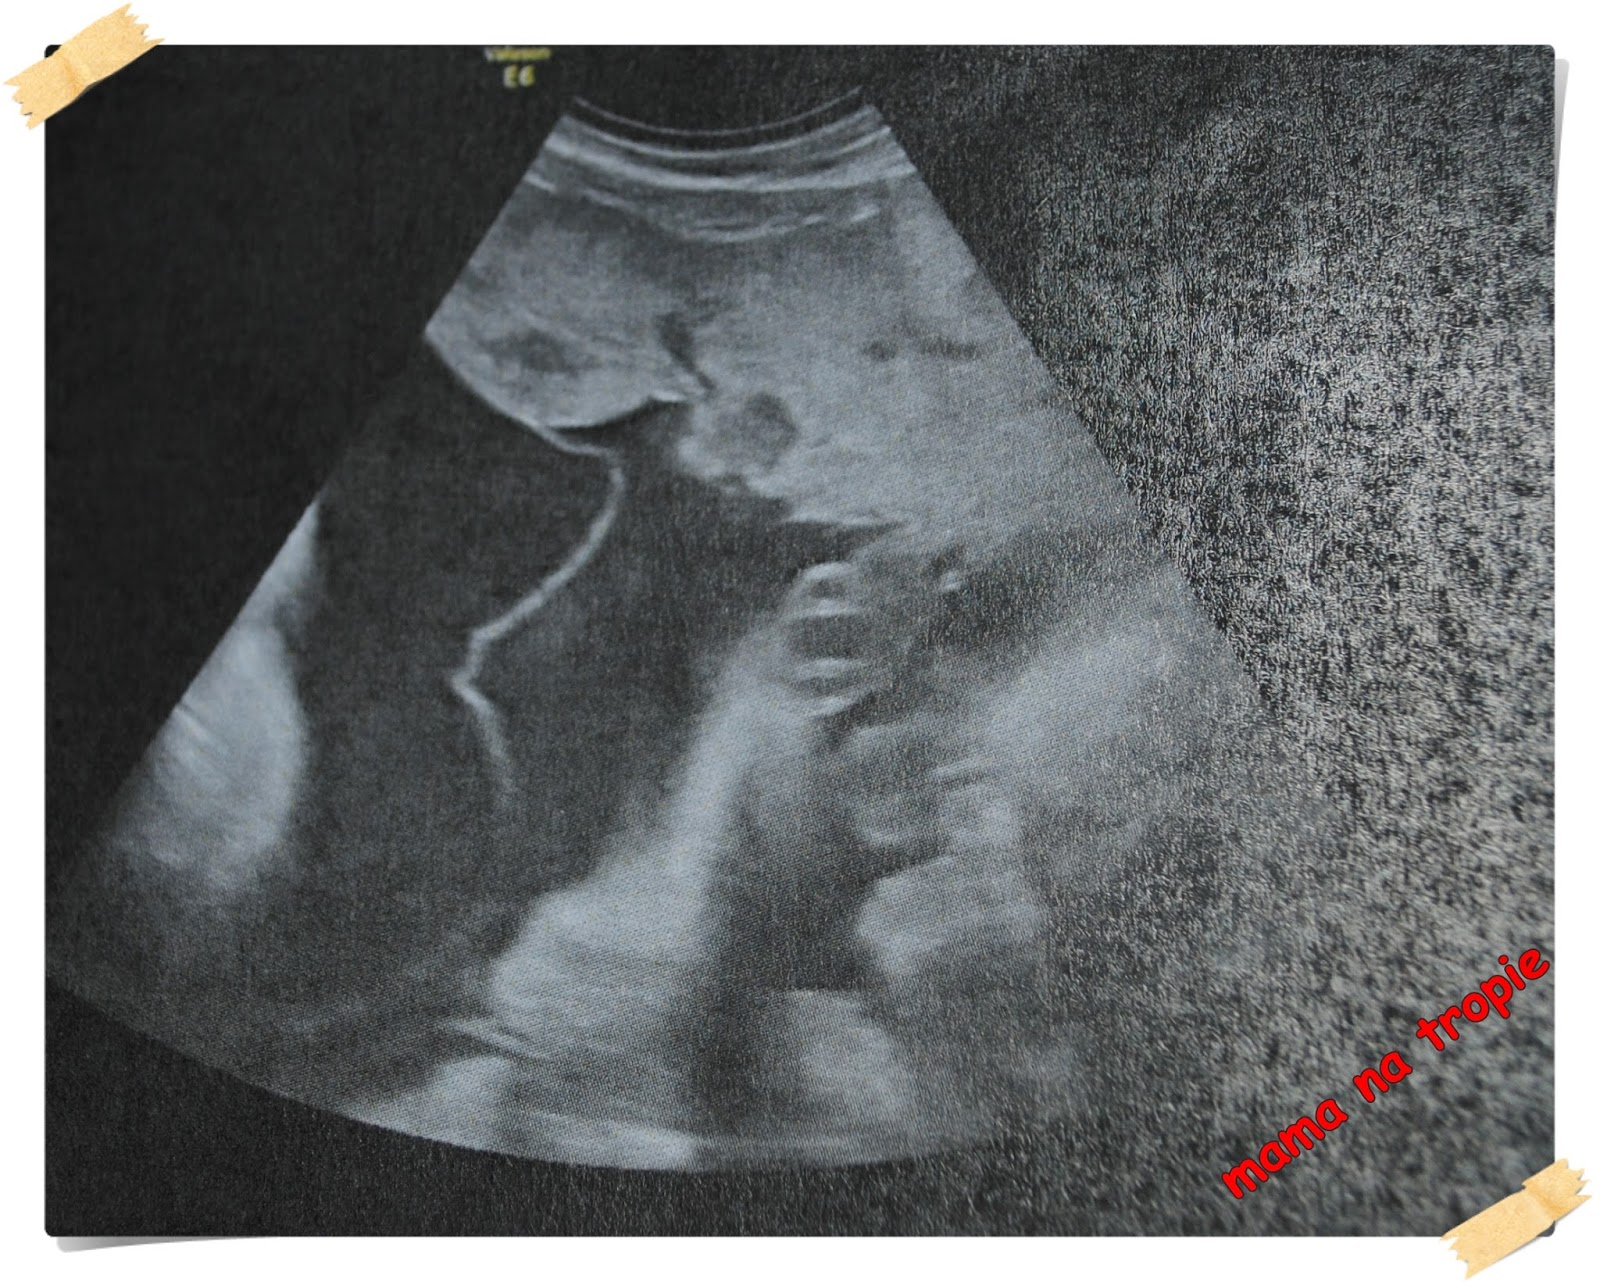

24-26 tydzień. Czas leci… maluchy rosną tak jakby były pojedyncze a nie we dwójkę, więc i matka ma coraz większe, odczuwalne fizycznie problemy. Na usg niestety coraz mniej widać, gniota się tam maluszki, chowają przytulając do siebie nawzajem oraz do ścian macicy czy też wskakując mi pod żebra. Tym razem chciałam Wam pokazać przepływy w pępowinie oraz w sercu jednego z bliźniaków – są jak najbardziej prawidłowe. A TTS-u ani widu ani słychu, choć lekarz ostrożnie zaznacza, że zdarzył mu się nawet taki który się zaczął w 30 tygodniu. Wyniki troszkę spadły jeśli chodzi o żelazo, więc dostałam do spożycia Sorbifer. Nie najgorszy w smaku i nie najtrudniejszy do spożycia, patrząc na to, że nie umiem totalnie łykać tabletek. Nie podrażnia mi tez żołądka więc jest nie najgorzej.

przepływy na pępowinie bliźniaków